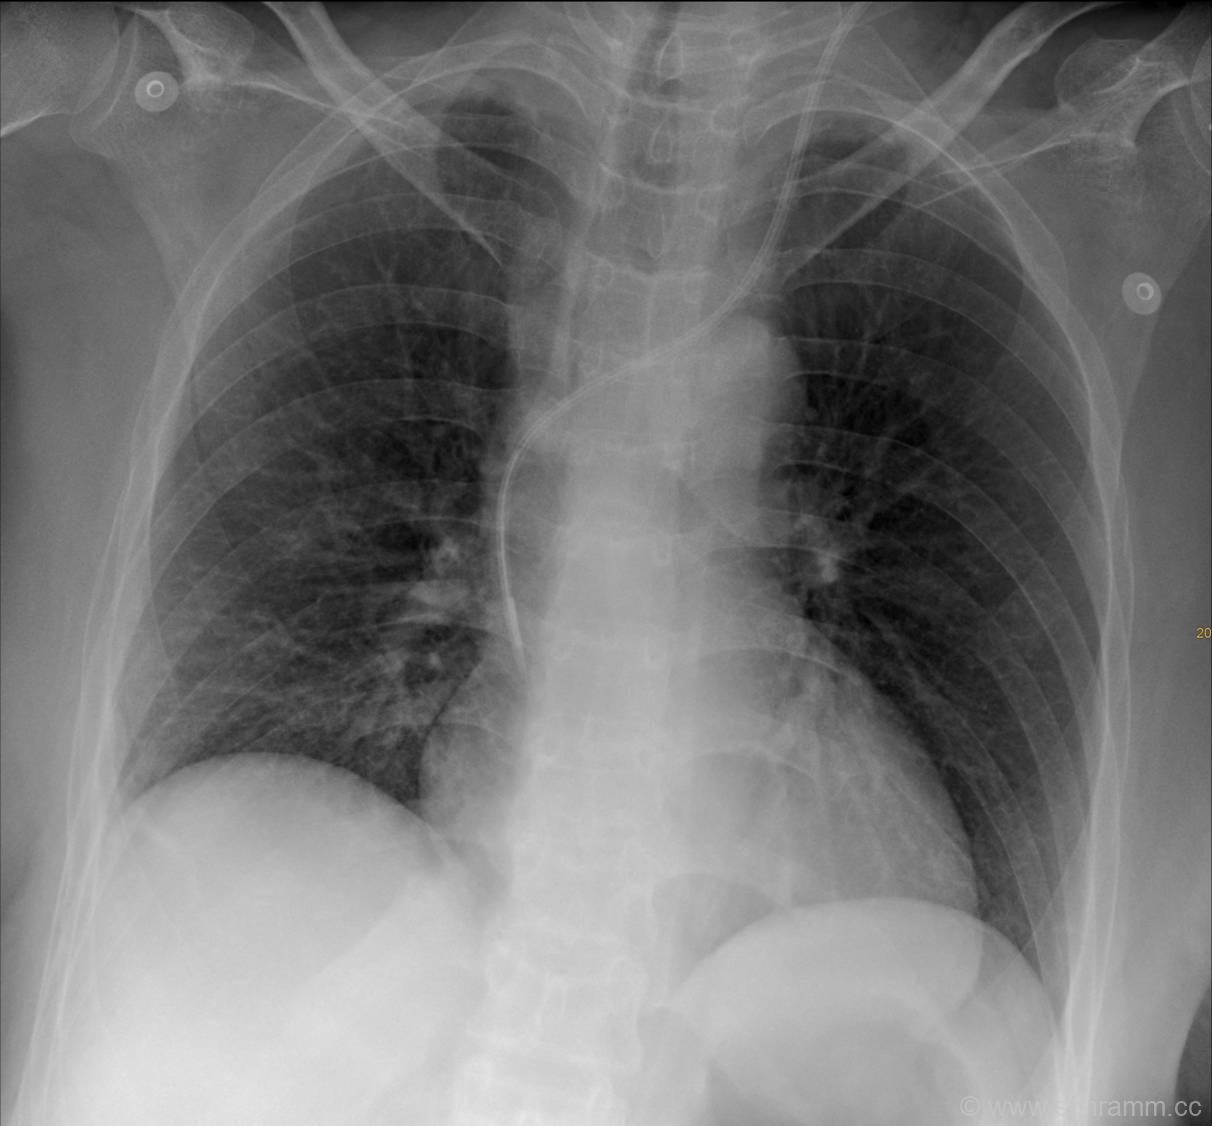

In diesem Thoraxröntgen findet sich ein zentraler Venenkatheter, welcher über die